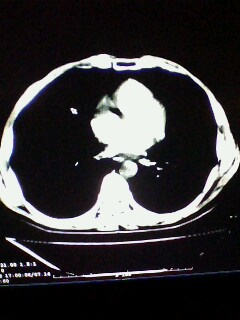

标题: CT28315:咳嗽咳痰咯血半月并胸痛 [打印本页]

标题: CT28315:咳嗽咳痰咯血半月并胸痛

1、纵膈窗效果不好,初步考虑左肺下叶感染性病灶,建议正规抗炎治疗后复查   2、右肺下叶陈旧性病灶伴局部胸膜增厚。

考虑左肺下叶周围型肺癌.图象欠清,请问病人贵更?

考虑左肺下叶周围型肺癌.

图像资料欠清,建议强化,考虑周围型肺癌。

左下肺肿块影,深分叶,考虑肺癌。

左下肺球形病灶,考虑:1:球形肺炎;2:周围型肺癌不除外,建议治疗后复查

不排除左肺下叶周围型肺癌可能!建议穿刺活检!

考虑左肺下叶周围型肺癌。

考虑左肺下叶周围型肺癌并阻塞性肺炎。

考虑左肺下叶周围型肺癌